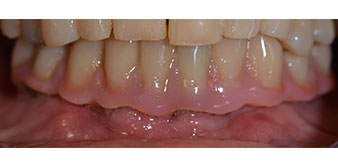

The 64-year-old patient presented with residual dentition of teeth 38, 33 and 43 and a clasp denture in the mandible (Fig. 1 and 2).

Fig. 2